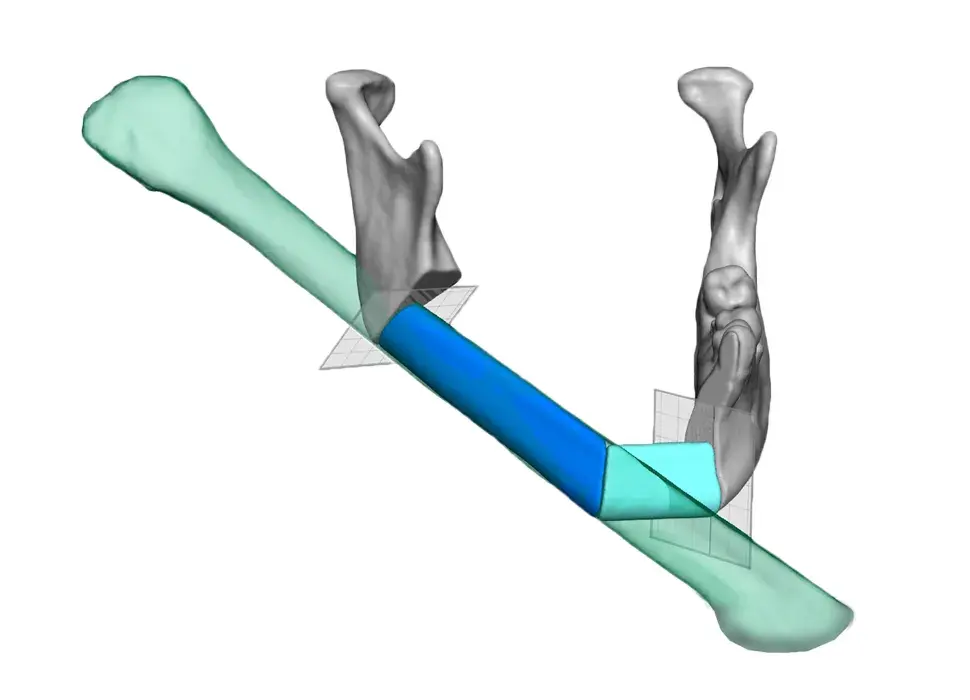

3D Systems' VSP® surgical planning solutions for craniomaxillofacial (CMF) applications received FDA clearance as a service-based approach to personalized surgery over 10 years ago.

3D Systems and Stryker Corporation have partnered to provide surgeons with best-in-class products and services for craniomaxillofacial surgeries. As a leader in personalized healthcare solutions, 3D Systems has planned and delivered devices for more than 140,000 patient-specific cases. The Stryker Craniomaxillofacial business specializes in providing patient-specific options and innovative solutions that help drive efficiencies in surgical suites. The combination of Stryker’s specialized team and advanced implants with 3D Systems' cutting-edge 3D printing technologies and expert consulting services positions both companies to provide a superior level of service to healthcare professionals who use these revolutionary solutions.